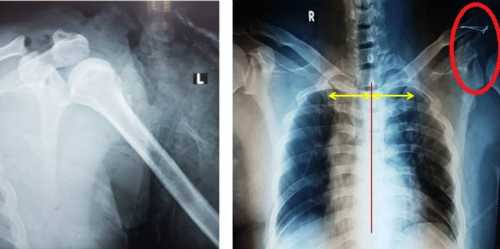

Bác sĩ Bệnh viện Chấn thương chỉnh hình TP HCM chẩn đoán bệnh nhân bị phân ly bả vai lồng ngực trái; vết thương vai trái dập nát gần toàn bộ cơ delta; gãy nát 2 tầng 2 xương cẳng tay trái; vết thương mô cái bàn tay trái; tổn thương bó mạch, đám rối thần kinh tay.

Theo BSCK II Phạm Mạnh Tân, phân ly bả vai lồng ngực (Scapulothoracic Dissociation) là chấn thương rất hiếm gặp trong y văn, khó chẩn đoán nếu không có kinh nghiệm nên dễ bỏ sót. Trường hợp bệnh nhân này được phát hiện và xử trí kịp thời nên không còn nguy cơ tử vong, giữ được chi (tay trái), không nhiễm trùng và khả năng phục hồi chức năng của chi cao.